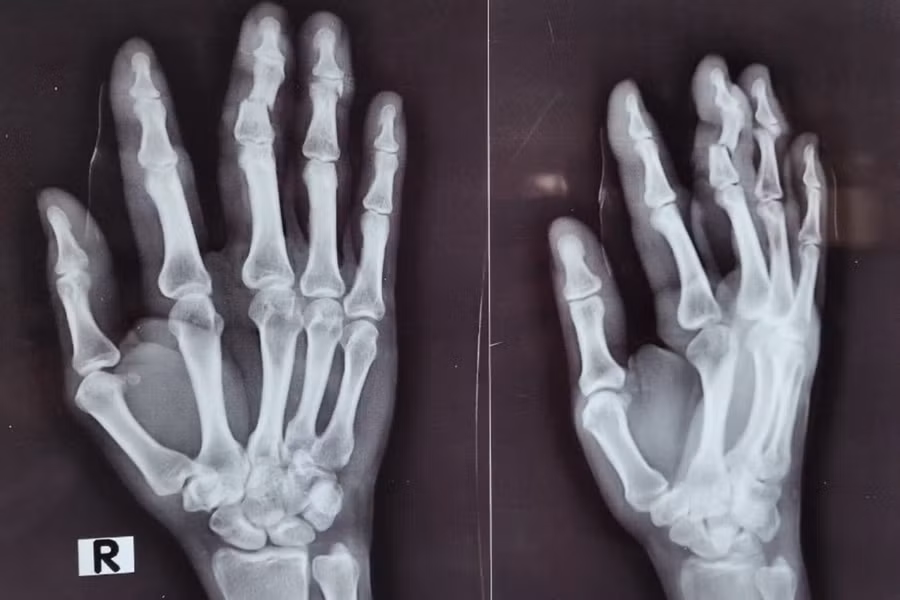

Ảnh chụp X-quang đánh giá các vết thương ở bàn tay của người phụ nữ. Ảnh: BVCC.

Cụ thể, khi đang làm việc, bệnh nhân nữ (51 tuổi) không may bị máy đập vào bàn tay phải, gây vết thương tại các ngón II, III, IV. Bệnh nhân nhanh chóng được đưa đến cấp cứu tại Bệnh viện Đa khoa Xuyên Á Tây Ninh.

Khoa Cấp cứu tiếp nhận bệnh nhân trong tình trạng vết thương phức tạp, đánh giá tổn thương thấy đứt gần lìa đốt giữa ngón III, gãy hở đốt xa ngón IV, vết thương đứt gân duỗi ngón II tay phải.